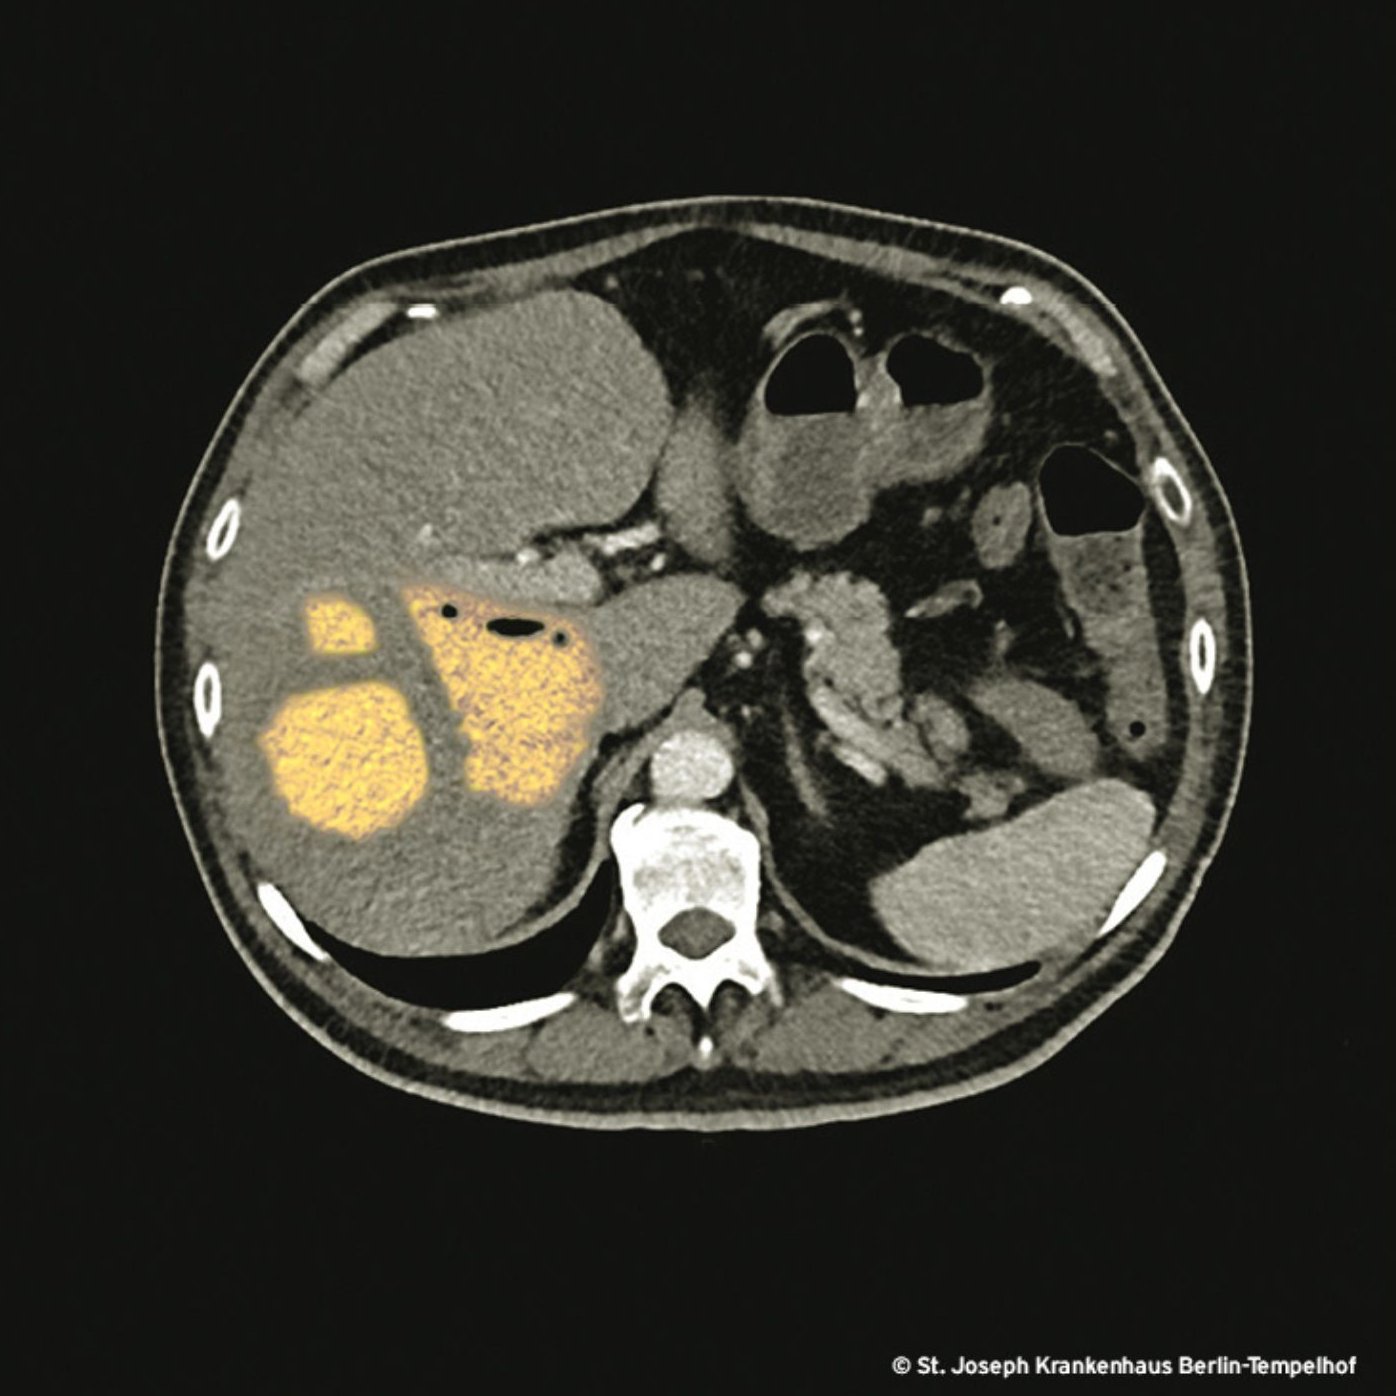

Leberabszesse, wie wir sie kennen, entstehen auf dem Boden von intraabdominellen Infektionen, hämatogen über die Pfortader oder aszendierend über die Gallenwege. Dieser Abszess hingegen ist bei einem (bis auf seine Zuckerkrankheit) gesunden Menschen aufgetreten, der im Vorfeld keine Infektion im Bauchraum hatte. Aus dem Punktat gelang der Nachweis eines aufstrebenden neuen Pathotyps der alt bekannten Klebsiella pneumoniae. Pathotyp? Das Wort fasst eine Gruppe von Organismen derselben Spezies zusammen, die ein charakteristisches Krankheitsbild verursachen (z.B. EHEC, EIEC, ETEC).

Klebsiellen des alten, klassischen Pathotyps verbinden wir mit Multiresistenz und nosokomialen Infektionen. Die neue Klebsielle ist anders: Sie fällt (noch) nicht durch ESBL-Bildung auf, sondern durch ihre extreme Aggressivität, was ihr den Spitznamen hypervirulente Klebsiella pneumoniae (hvKp) eingebracht hat. In einigen Regionen Asiens und den Pazifikanrainerstaaten ist sie zu einem relevanten Problem geworden. Patient*innen mit schlecht eingestelltem Diabetes mellitus erkranken häufiger schwer. Neben ambulant erworbenen Leberabszessen kann hvKp multiple oder metastatische Infektionen im ganzen Körper hervorrufen. Diese, für Enterobacteriaceae untypische Eigenschaft erinnert an die Virulenz von Staphylococcus aureus. Deshalb ist das diagnostische Workup bei beiden Spezies ähnlich umfangreich.

Unser Patient hatte Glück, weil andere Organe, insbesondere Auge, Prostata und das ZNS ausgespart blieben. Der Abszess wurde erfolgreich drainiert. Die Antibiotikatherapie wurde fokussiert mit Ampicillin/Sulbactam, dem Betalaktam mit dem schmalsten Spektrum durchgeführt. Die Therapiedauer betrug vier Wochen.